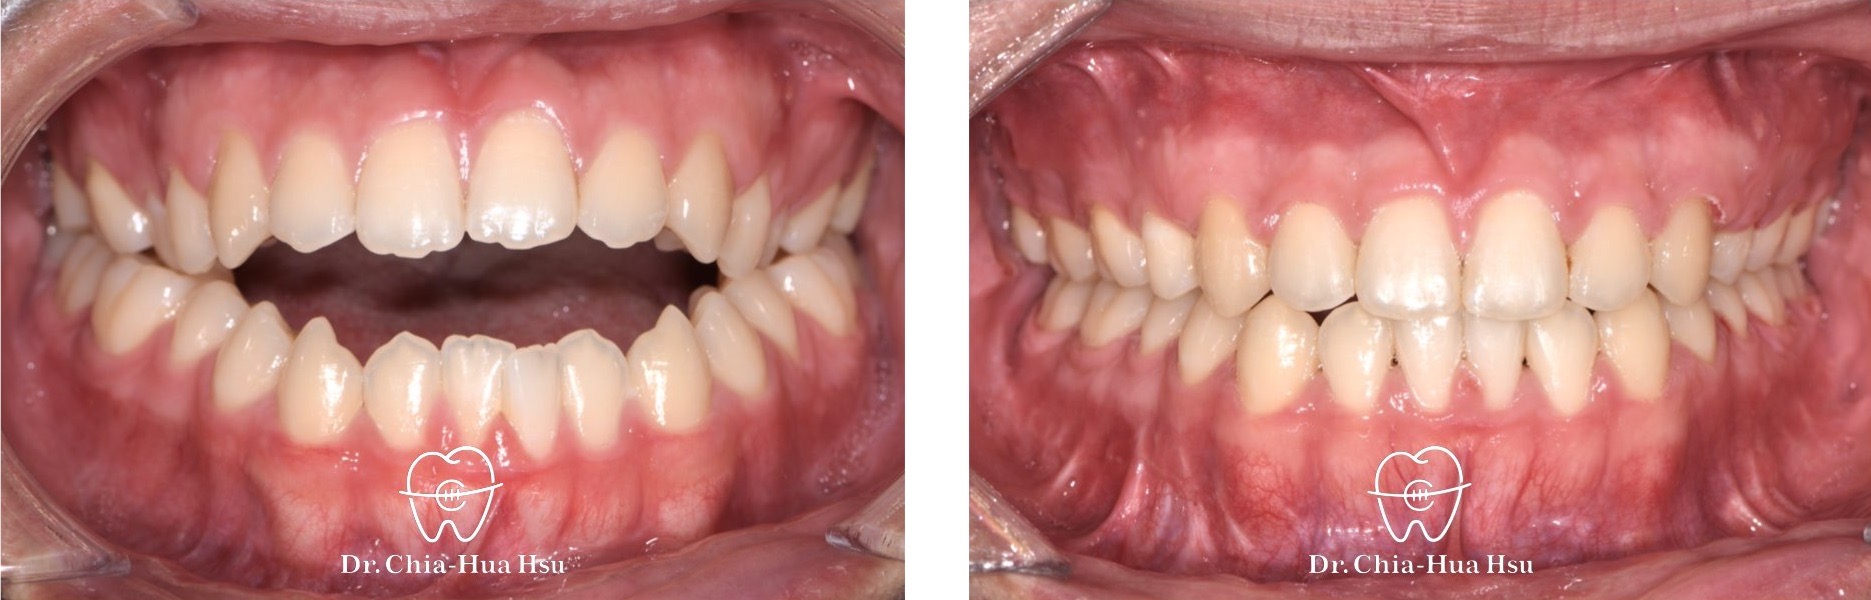

戽斗、開咬、齒列不正

• 病患主訴:戽斗、前牙開咬。

• 問題分析:患者是標準的骨骼三類咬合(Skeletal Class III),下巴明顯較長,還有上顎牙弓過窄、開咬以及齒列不正。

• 治療方式:使用傳統金屬矯正器,合併正顎手術(雙顎),上顎拔除兩顆小臼齒以利手術方式進行上顎牙弓擴寬。

• 治療時間:1 年 7 個月。

• 治療結果:齒列排齊,咬合功能恢復,外觀更和諧。

治療前

治療後